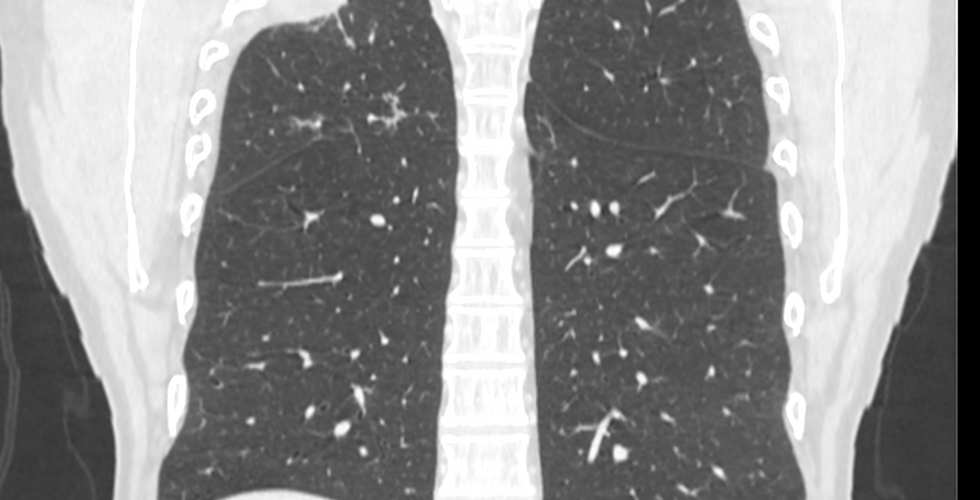

Un hombre de 45 años es diagnosticado con un tumor de pulmón en el lóbulo superior derecho. El tumor invadía la pared torácica y el tratamiento indicado fue una cirugía resectiva luego de recibir quimioterapia y radioterapia neoadyuvante.

Para la planificación de la misma, se utilizo un modelo anatómico a medida del paciente que replicaba la anatomía a escala real.

El Dr. Nicolás contó con un modelo 3D virtual y uno físico que le permitieron aclarar todas las dudas acerca de la anatomía y el alcance de la masa anómala que las imágenes bidimensionales no podían resolver. Esto, le dio la posibilidad de optimizar los márgenes de resección.

El plan quirúrgico mini-invasivo elegido fue una lobectomía superior derecha por cirugía toracoscópica uniportal asistida por video (UVATS) con resección costal. El biomodelo físico fue de utilidad para visualizar y proyectar cómo realizarían el procedimiento seleccionado para el paciente.

Dentro del quirófano también se utilizó el modelo 3D anatómico el cual se consultó en varias oportunidades para guiar el abordaje hacia el tumor y fue fundamental para reconocer los puntos de reparo en la costilla que delimitaban la resección, indicó el Dr. Nicolás.